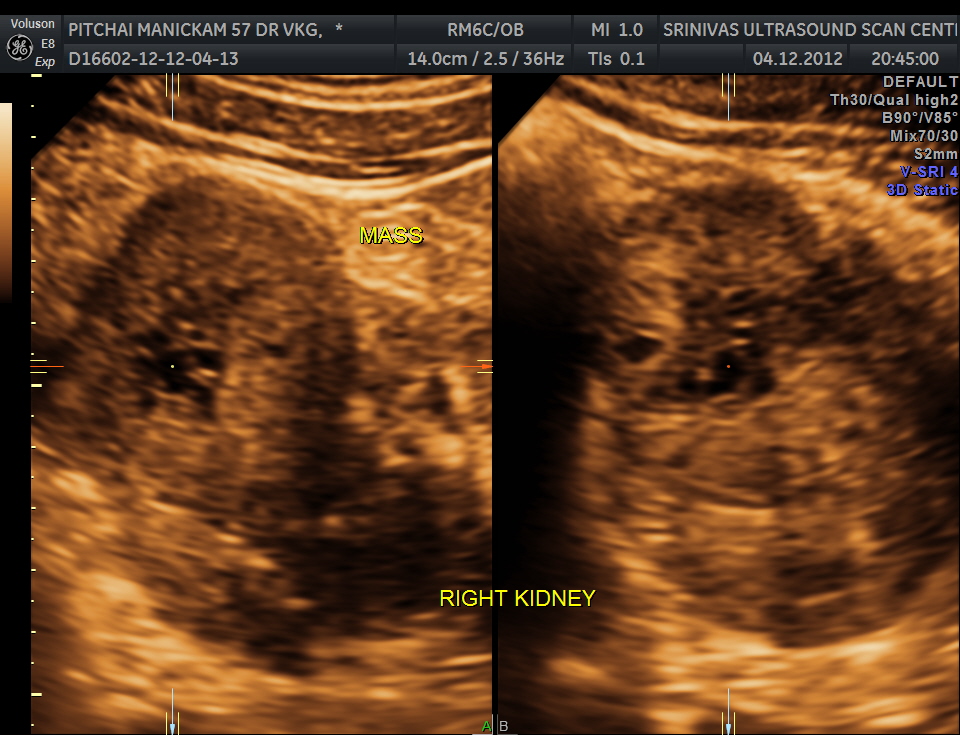

The right kidney pictures are given below. Mass lesion seen in the lower pole .

3 D images are given below.

the next is a reconstructed image of the mass.